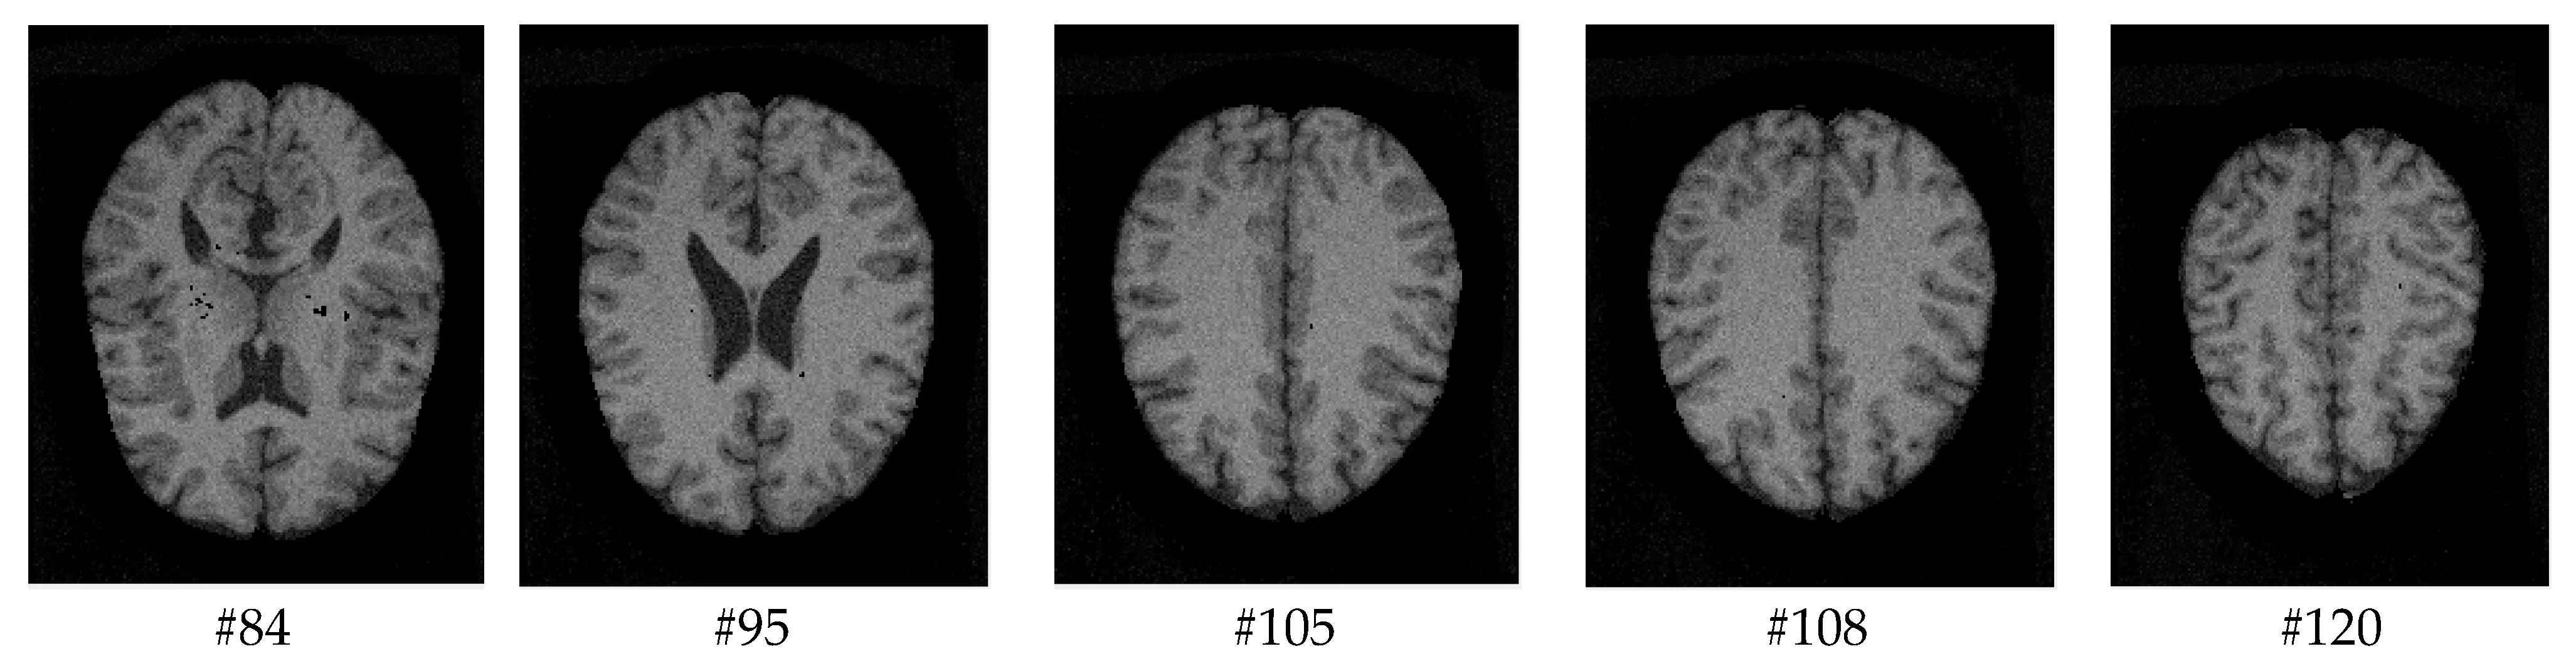

As mentioned before, the images of the first five datasets in Table 3 were used to evaluate the performance of the HMRF-WOA. Figure 1, Figure 2, Figure 3, Figure 4 and Figure 5 show some slices of a T1-weighted image (slices: 84, 95, 105, 108, 120). These brain images correspond to the slices under different types of conditions, such as database type, dimension image, noise level, intensity non-uniformity level, and slice thickness (mm). In Table 1, rows 1 to 5 summarize the parameters of Figure 1, Figure 2, Figure 3, Figure 4 and Figure 5, respectively. Figure 6 represents the ground truth segmentation of slices 84, 95, 105, 108, and 120. In this figure, each column contains the three tissues, GM, WM, and CSF, of each slice. Figure 7, Figure 8, Figure 9, Figure 10 and Figure 11 show the segmentation results, where the four tissues (BG, GM, WM, and CSF) are shown with different colors. The yellow, red, and green colors represent the segmented regions of GM, WM, and CSF, respectively. As we can also see from these figures, the resulting segmented images in Figure 7, Figure 8, Figure 9, Figure 10 and Figure 11 are almost close to the initial images in Figure 1, Figure 2, Figure 3, Figure 4 and Figure 5.

Figure 5. Slices with Noise = 9%, INU = 40% of database 5.